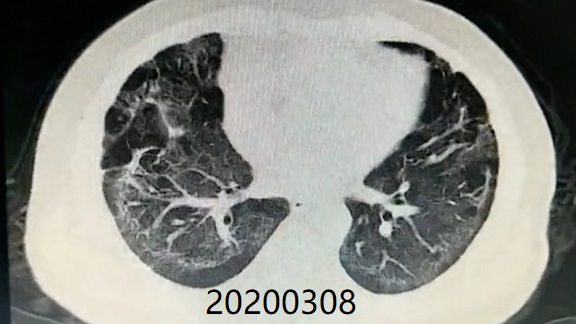

Comparison of CT imaging of chest before and after treatment with the patient (Mr. Zhang)